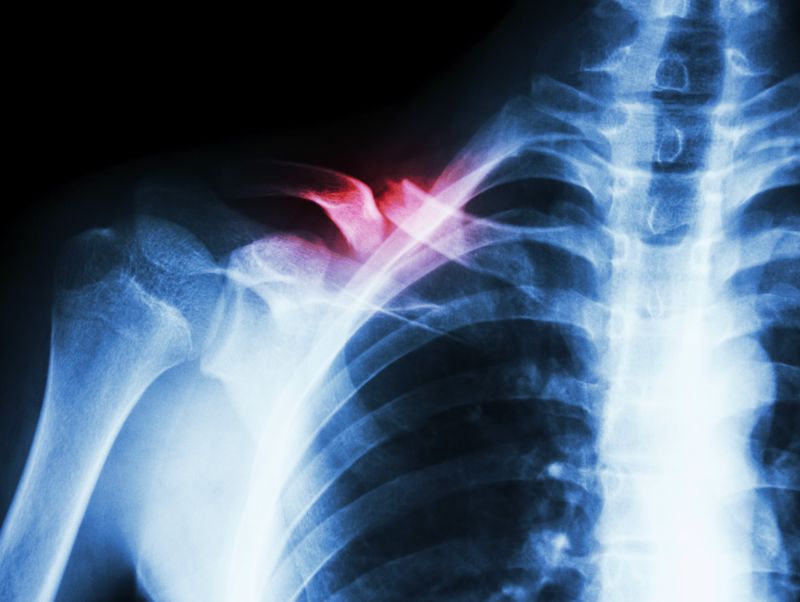

如果病患的肩胛骨骨折,这种情况局部的疼痛是非常明显的,患者在睡觉的时候要注意,一定要尽量的侧卧,同时不能朝骨折的这一侧睡,要没有骨折的那面朝下卧或者平卧也可以。不建议肩骨折的那一侧朝下睡觉,因为容易造成骨折移位,那么疼痛就是非常剧烈的。睡觉时一定要注意不要大幅拉扯到受伤部位或者上肢,避免再次扭伤。如果骨折部位有移位情况出现的话,那就需要再次处理了。

肩胛骨骨折后怎么睡觉

1、肩胛骨骨折的患者睡觉时候,不要向患侧侧身压迫到肩胛骨。

2、平躺或是向健侧侧身都没有问题的,可以尽量保持平卧方式,避免上肢大幅度活动平时要三角巾悬吊保护。

3、如果是右侧的肩胛骨骨折,就得左侧卧位。如果是左侧的肩胛骨骨折,就要右侧卧位。